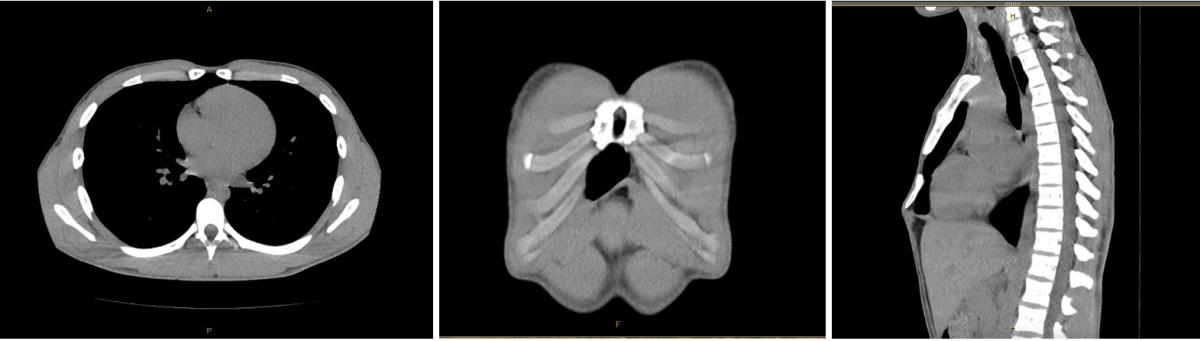

A 16-year-old male with no past medical history initially presented for evaluation of xiphodynia. He reported that he had a prominent protrusion from the inferior aspect of his sternum, which caused him pain when lying prone and when diving during volleyball. A preoperative computed tomography (CT) scan incidentally revealed a 2.0 cm x 2.5 cm sternal foramen in the lower third of his sternum (figure 1). Given that there was evidence of healthy and intact surrounding cortical bone, sternal reconstruction was deferred, and he proceeded with xiphoid resection.

Figure 1: Computed tomography views of an inferior foramen.